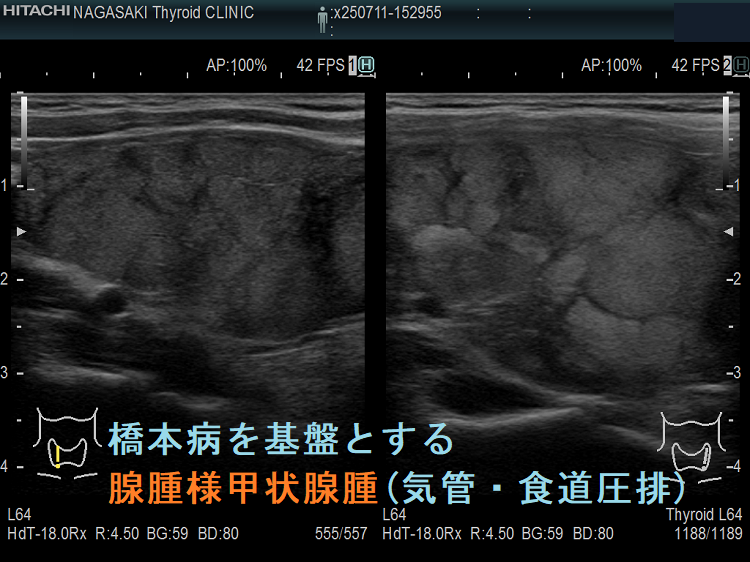

ケース④ 橋本病を基盤とする腺腫様甲状腺腫(気管・食道圧排)

橋本病を基盤とする腺腫様甲状腺腫(気管・食道圧排) 矢状断;等エコーなので甲状腺悪性リンパ腫が隠れているようには見えないが、潜在性甲状腺癌(甲状腺ラテント癌)が存在する可能性は否定できない。かなり気道圧迫している。